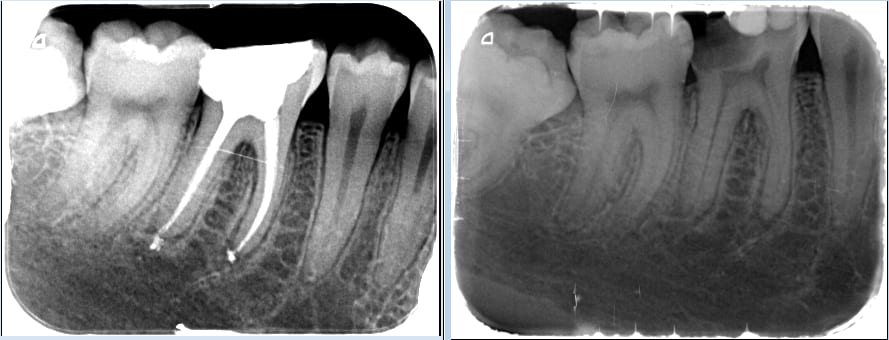

Premier retraitement avec le nouveau ciment.

Le pate pate, c'est pratique, je peux le spatuler sur un sachet d'autoclave ouvert.

PS: joli l'endo de la 6